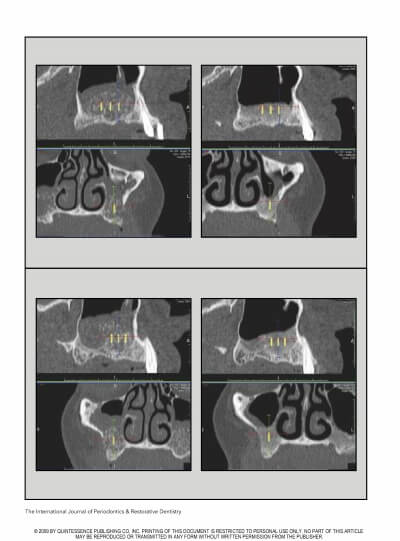

MAXILLARY SINUS AUGMENTATION- 3 CASES

SINUS FLOOR AUGMENTATION WITH HYDROPNEUMATIC TECHNIQUE

SINUS AUGMENTATION PROCEDURES